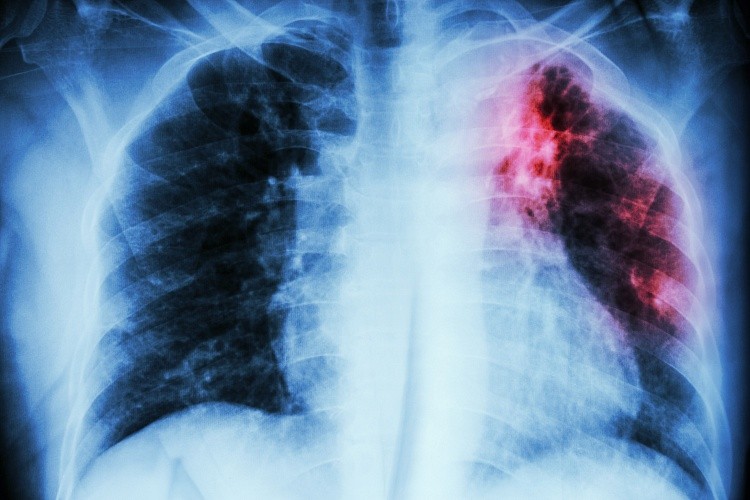

Туберкулез на рентгене: описание, показания к проведению . . .

Флюорография при туберкулезе: проведение и описание полученных результатов . Может ли рентген не показать туберкулез? Туберкулез легких является одним из самых опасных заболеваний, нуждающихся в срочном и современном лечении .